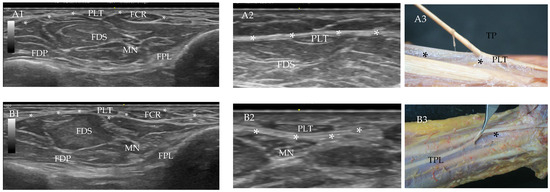

Palmaris Longus Muscle and Its Variations: Ultrasound, Anatomical and Histological Study with Clinical and Surgical Applications

Background/objective: The palmaris longus muscle is a variable and often inconsistent muscle in the anterior compartment of the forearm. This fusiform-shaped muscle originates at the medial epicondyle of the humerus bone following a long and narrow tendon that inserts at the palmar aponeurosis. [...] Read more.

Background/objective: The palmaris longus muscle is a variable and often inconsistent muscle in the anterior compartment of the forearm. This fusiform-shaped muscle originates at the medial epicondyle of the humerus bone following a long and narrow tendon that inserts at the palmar aponeurosis. That tendon is used in reconstructive surgery, and for this reason, detailed information from an ultrasound is used to detect the tendon and the possible variations in the muscle. The present study aimed to investigate the palmaris longus muscle and its variations through ultrasound, anatomical, and histological analysis with clinical and surgical applications. Methods: A total of 72 upper limbs from 33 females and 39 males, 32 right and 40 left, were evaluated in ultrasound, anatomical, and histological studies. The main objective was to prove the existence of the palmaris longus muscle and its variations, as well as to measure the tendon for surgical applications. Results: Ultrasound analysis showed that it is possible to determine the existence of the muscle (76.4%) and its variations (23.6%), as well as its absence (15.3%). The anatomical results proved the ultrasound results. The width of the tendon was between 0.4 and 0.38 mm. by ultrasound and anatomical analysis. Also, normal palmaris longus tendons were not a direct cause of compression of the median nerve. Conclusions: It is important to confirm the existence and possible variations in the palmaris longus muscle and tendon through ultrasound before surgical reconstruction and for clinical diagnostics. Full article